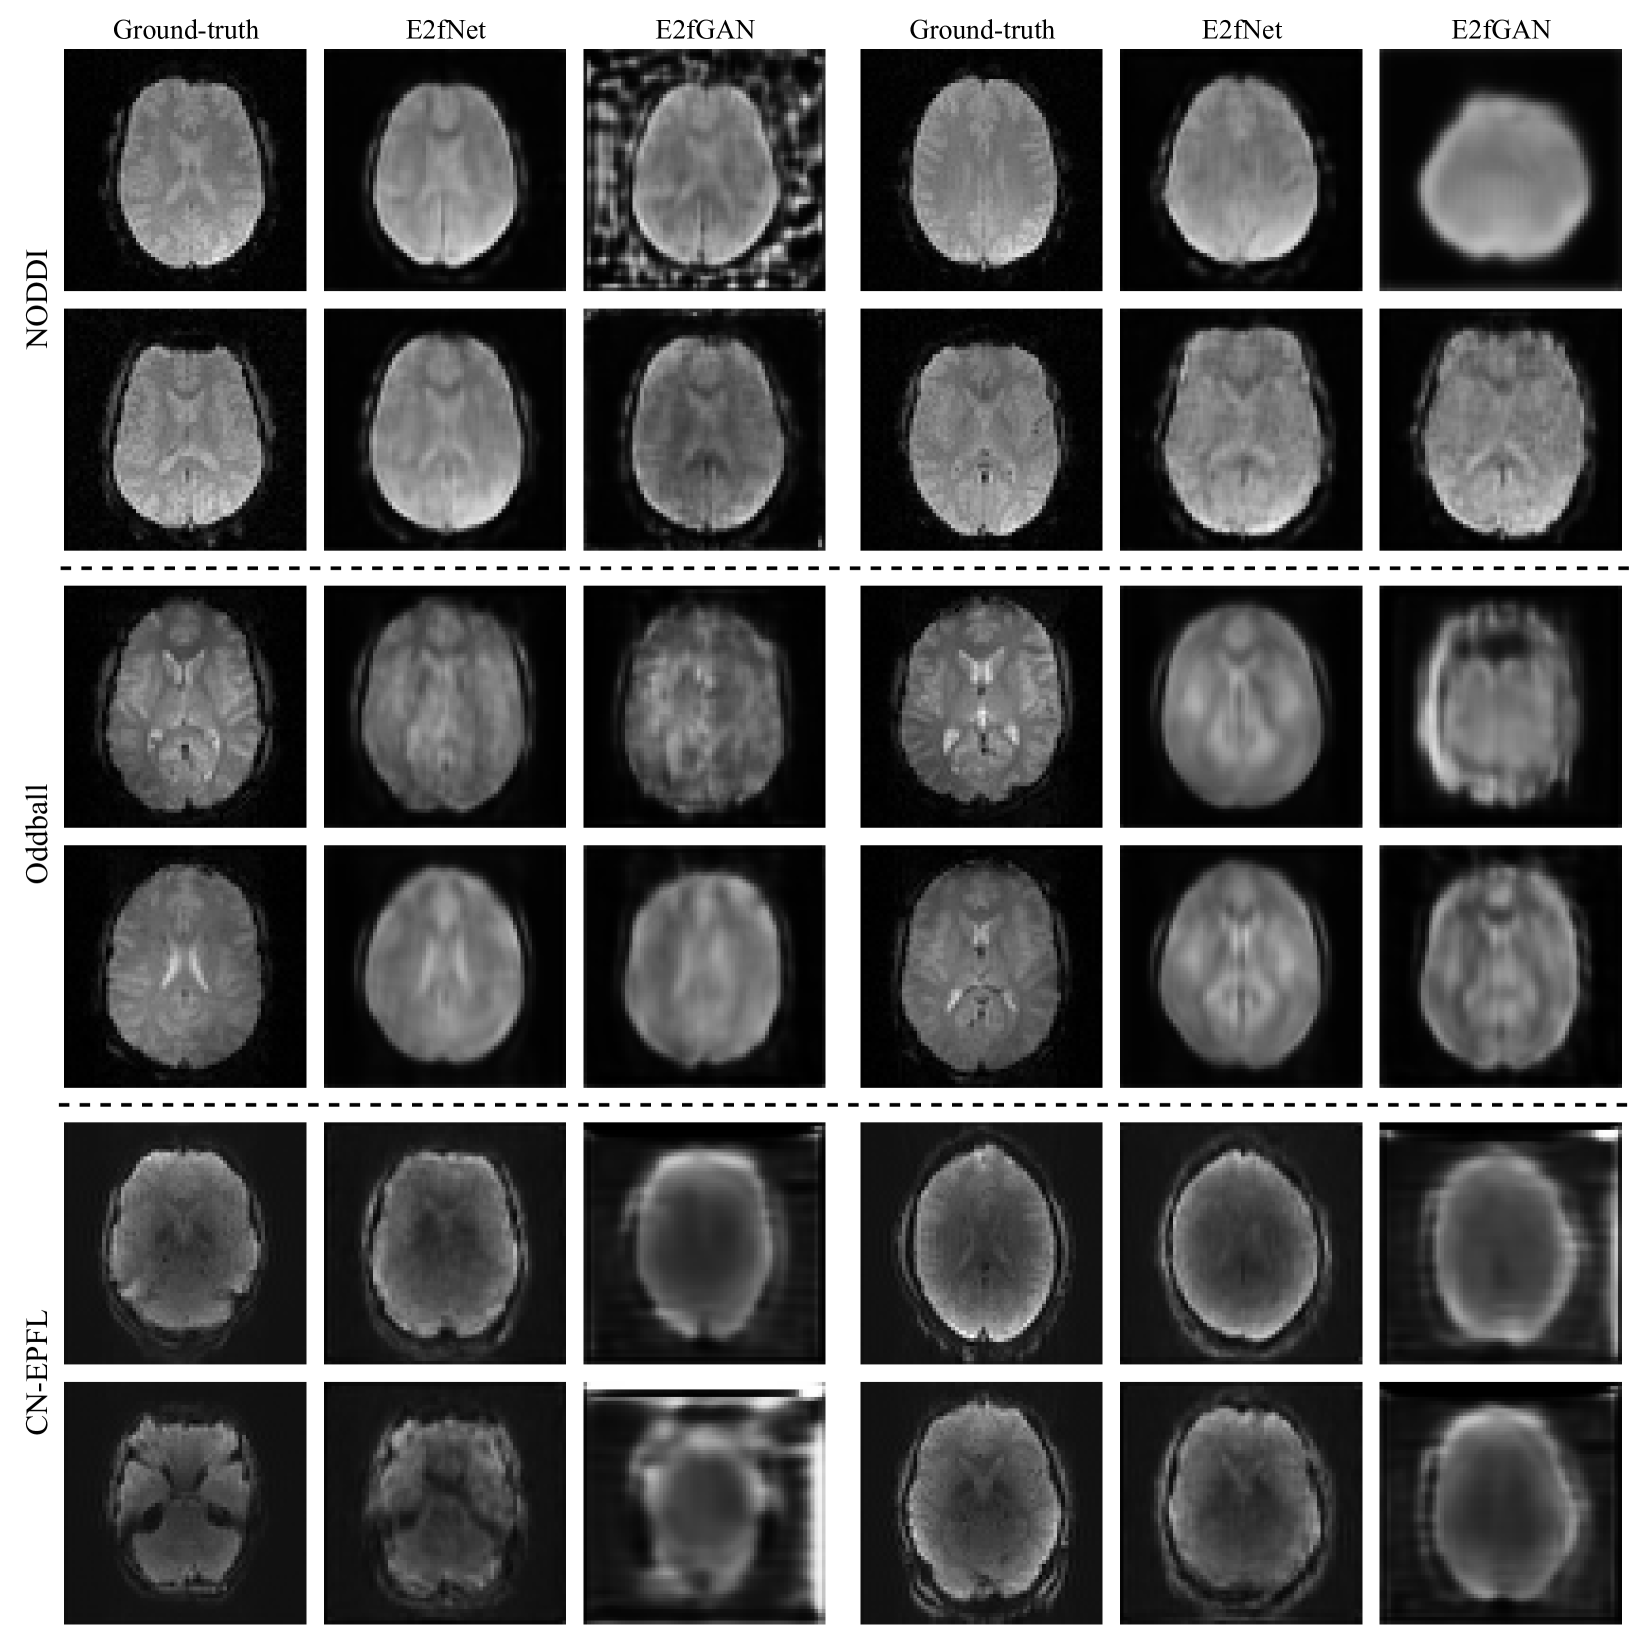

Refer to caption

Figure 2: Visual comparison of the generated fMRI by E2fNet and E2fGAN models on the NODDI, Oddball, and CN-EPFL datasets.

To provide a more comprehensive evaluation, we compared E2fNet with the GAN-based E2fGAN model, which uses E2fNet as the generator. Fig. 2 presents a visual comparison of E2fNet and E2fGAN across the three datasets. During the experiments, we observed that training the GAN model was often unstable, leading to unexpected outputs (Fig. 2, first row of the NODDI and Oddball datasets, first example in the second row of the CN-EPFL dataset). This instability contributed to E2fGAN’s lower SSIM and PSNR scores compared to E2fNet. Nevertheless, in some cases, E2fGAN produced visually sharper fMRI volumes. Future work could explore improvements by adopting more robust GAN training strategies.

It is important to note that SSIM and PSNR metrics may be sometimes less reliable when evaluating small or blurry images. For instance, while E2fGAN frequently generated oversmoothed and less detailed results on the CN-EPFL dataset, it still achieved seemingly reasonable SSIM and PSNR scores. We believe developing better similarity metrics could help address this limitation. There is still room for improvement, and we plan to investigate these aspects in future work.